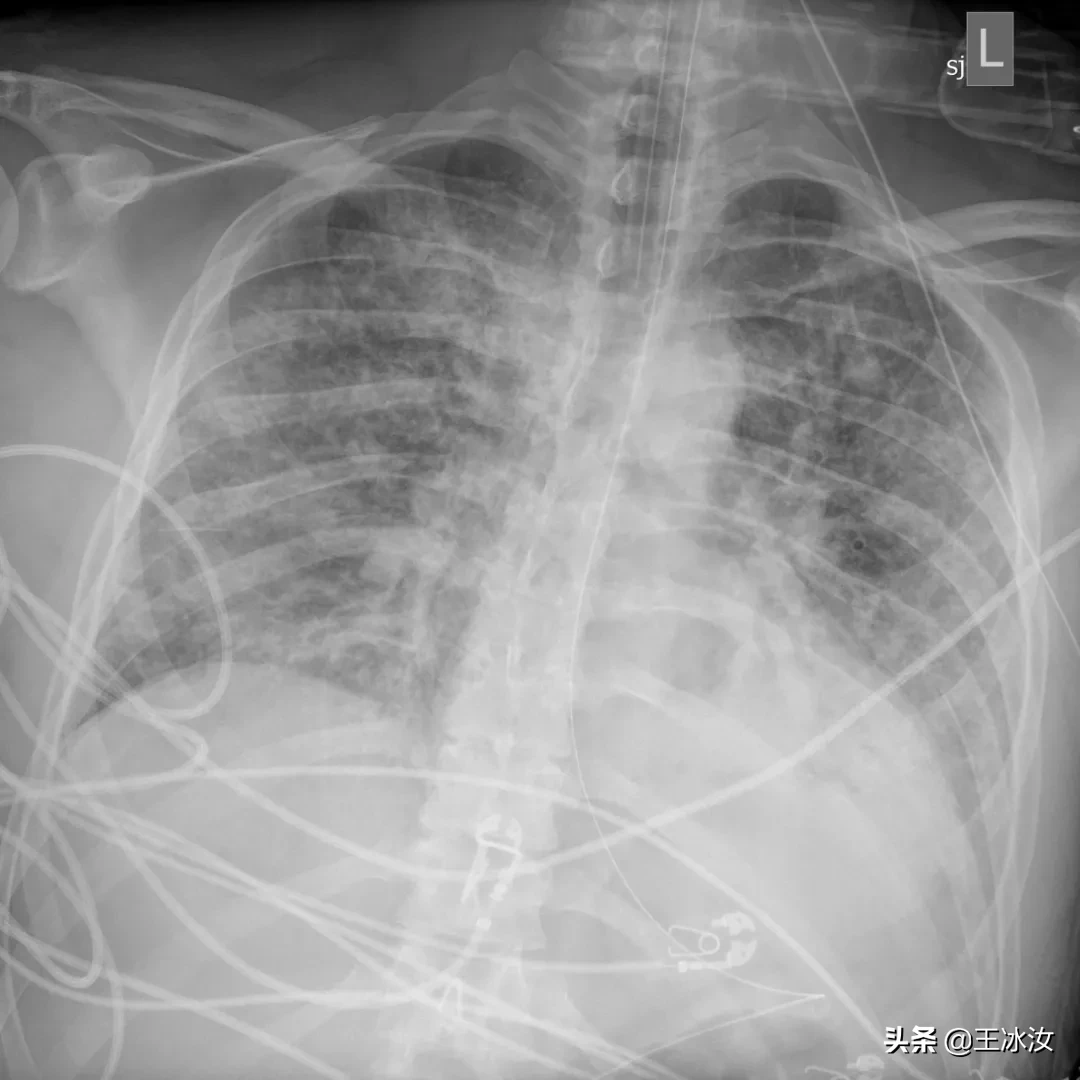

这是我见过最糟糕的胸片

在胸部拍片检查中,他的肺部看起来和旁边的骨头一样白,整个肺部已经没有了含气的地方(肺内实变之后含气量减少,密度增高,颜色变白),他的医生库里尔(Paul Currier)说:“这是我见过最糟糕的胸部拍片”。

3月14日,贝洛的第一张肺部X光,肺部充满液体和炎性细胞

虽然医生已经放出了大绝招,但是贝洛胸片越来越糟。他第一次拍的胸片虽然显示出明显的积液和炎症,但还可以看出肺脏影像,3月18日,胸片所见恶化,但肺的轮廓仍然可见。到3月20日时,他的肺部表现基本上就是我们所说的“大白肺”(完全实变,肺影全部变白)